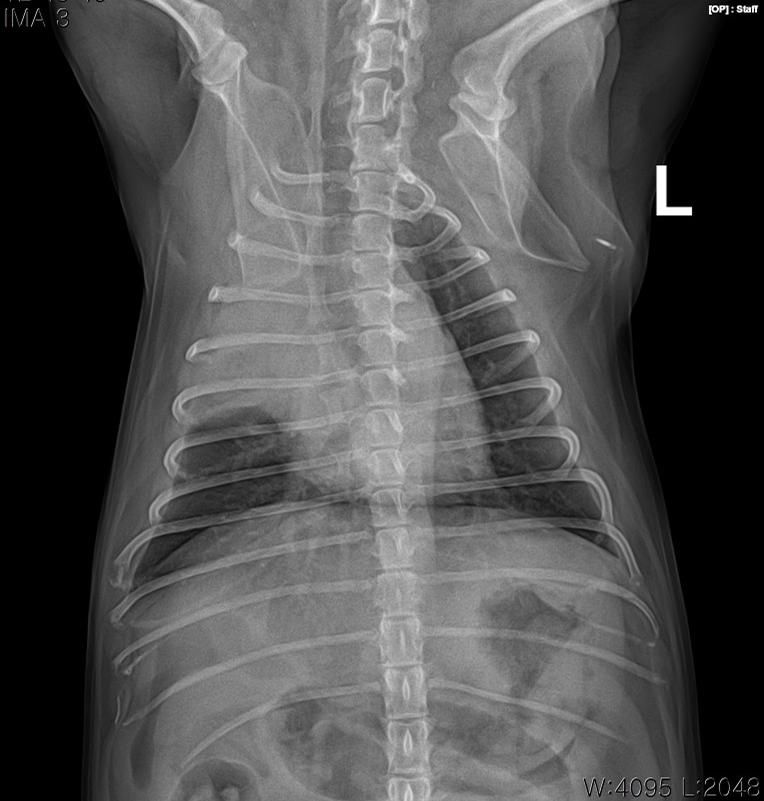

강아지 폐 종양 기수(진행 현황)에 대해 궁금합니다

엑스레이와 CT를 보았을 때, 강아지 폐암이 몇 달 정도 진행된건지 알 수 있을까요?

약 2~3주간 기침, 가래 증상만 있던 상태입니다.

폐종양은 보통 아무증상없이 수개월~수년에 걸쳐 발생하는게 일반적이나 드문경우 수주에 걸쳐 하게 커지기 때문에 영상검사 결과만으로 발생 기간을 추정할 수 없습니다.